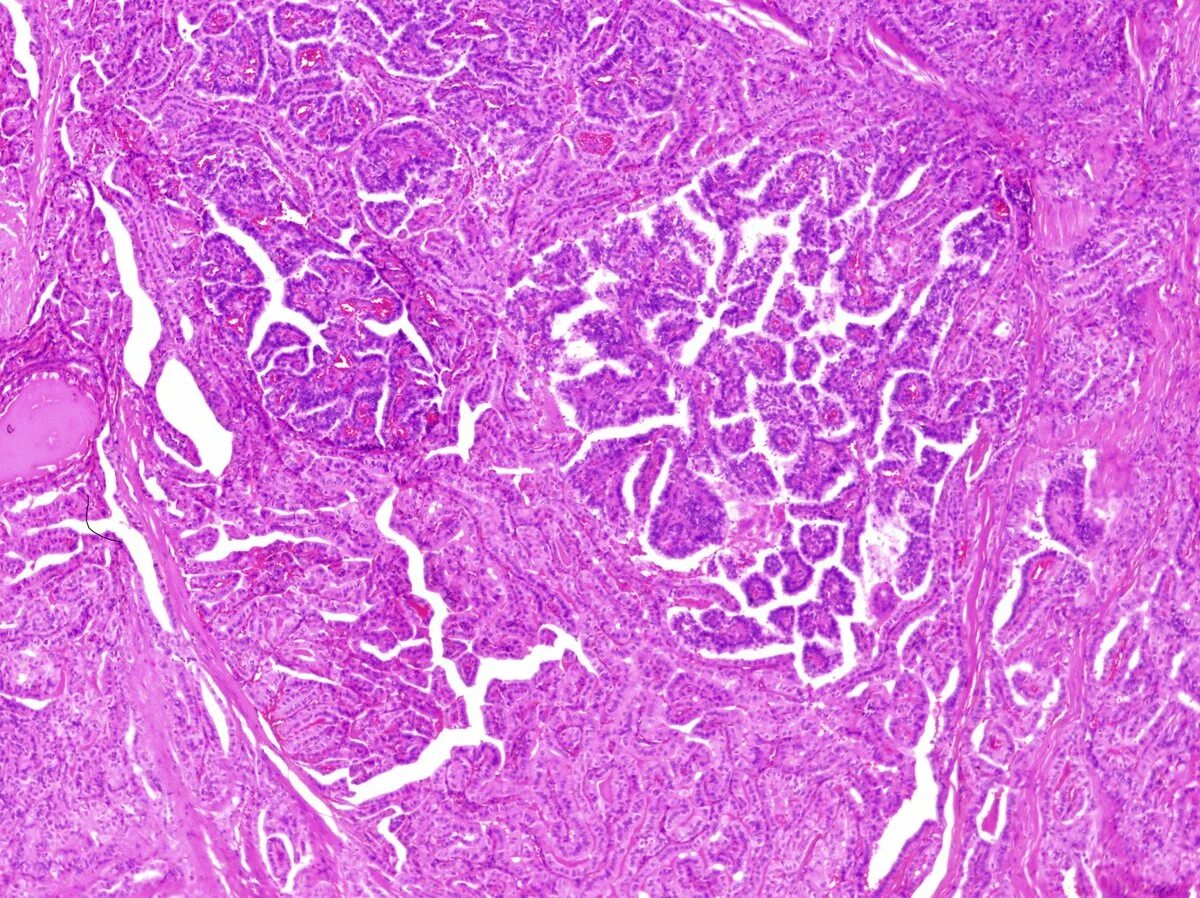

Гистологическое исследование почек